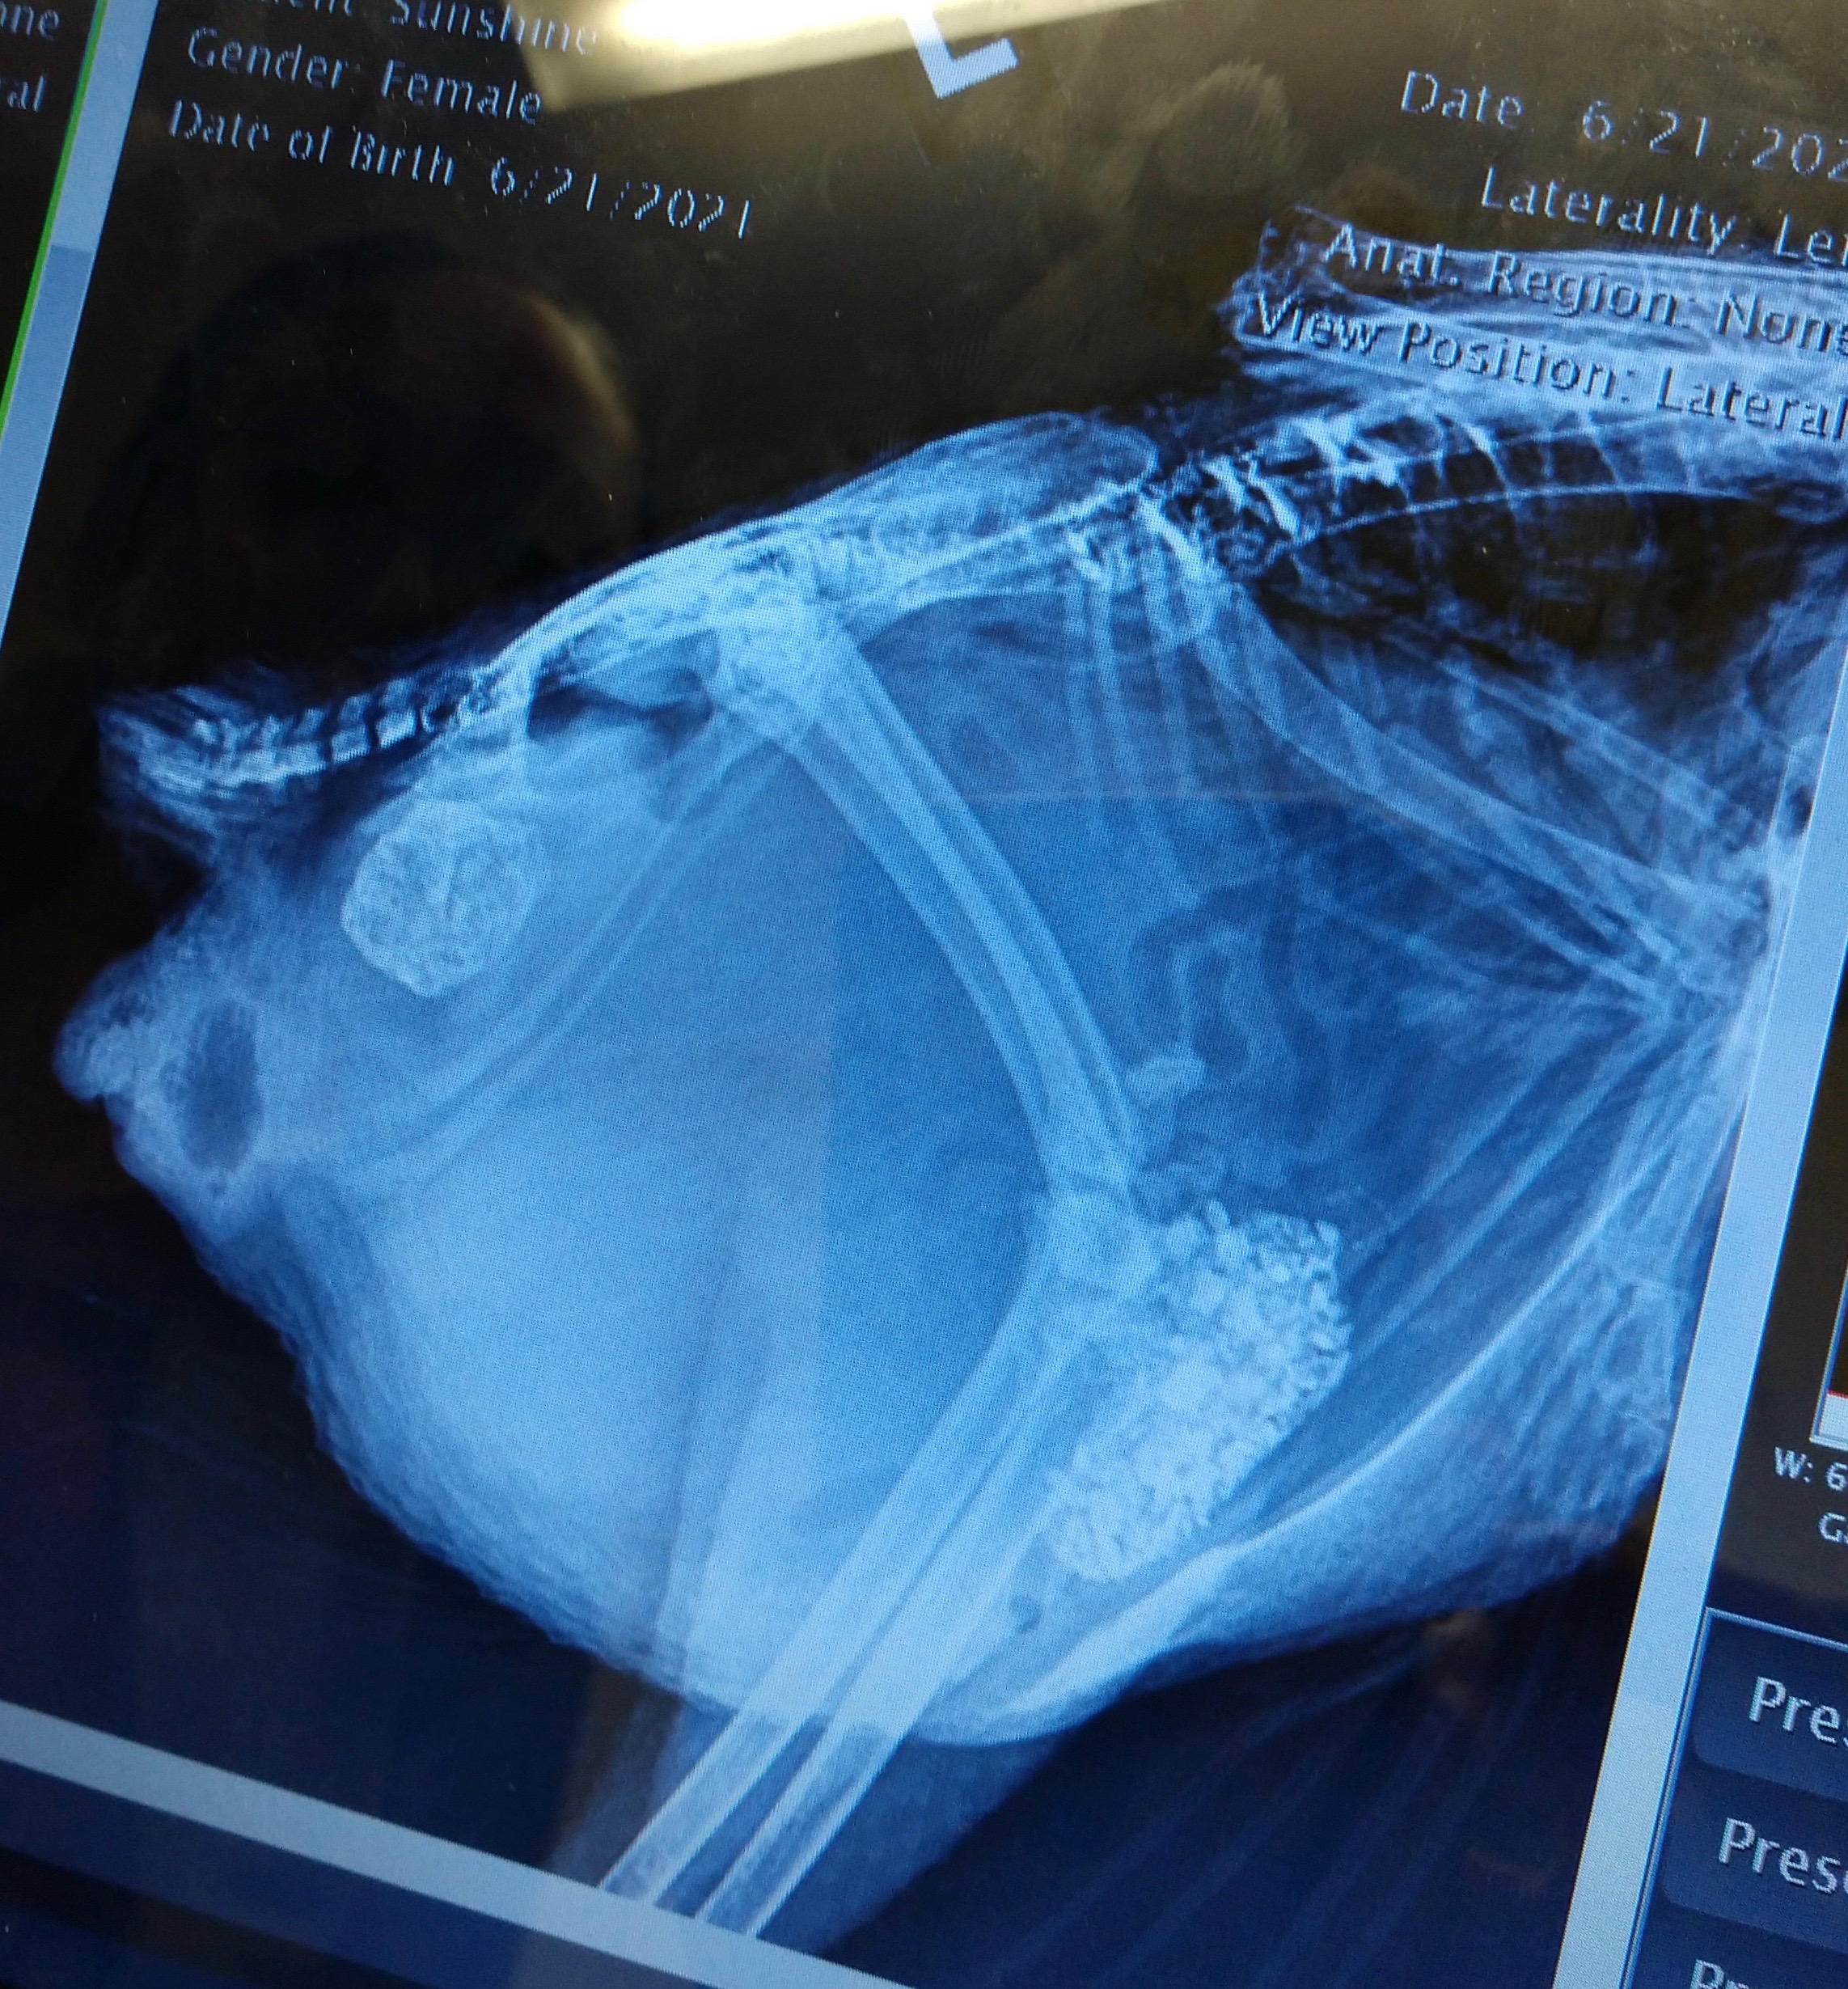

You’ll note that in some of the x-rays you can see a mass that looks like a ball of crumpled aluminum foil in her oviduct region. Those images are from the first visit, the ones with it missing are after she passed that obstruction. The mass itself is what’s in the Ziploc bag, both intact and after the vet broke it apart to examine contents. I wish we could have gotten a cross-section image, but at the time I felt it might be important for the vet to see exactly how it came out and cross reference to confirm nothing appeared to have been left behind.

Can you spot something important that our vet overlooked? We still haven’t been able to get a very clear picture of what’s going on apart from that blockage, but suspect something is, just based on the continuing digestive issues and apparent fluid still present at the second x-ray. I feel like she’s laying internally periodically and reabsorbing fluid between. Outwardly, she is acting like her system is on and functioning, but nothing comes of her efforts, so that has me concerned that she is doing something and it’s just not making it’s way out. I imagine septic EYP can be ruled out, as I don’t think we would be seeing these rebounds of full energy/appetite if anything had gone septic. She has good and bad days, and the bad ones always go hand-in-hand with the watery poop. She’s definitely got us scratching our heads.

Dr Bowes: The vet did a great job of the x-rays. They indicate the ureters are full of crates, a sign of dehydration, the intestines look normal, there is a lot of internal fat. The mass is a collection of debris from the oviduct. It is crumbly and friable, the result of a hemorrhagic component. The intestines appear to be bunched up. There is something obstructing the full view of the abdomen. Is that fat or yolk peritonitis?